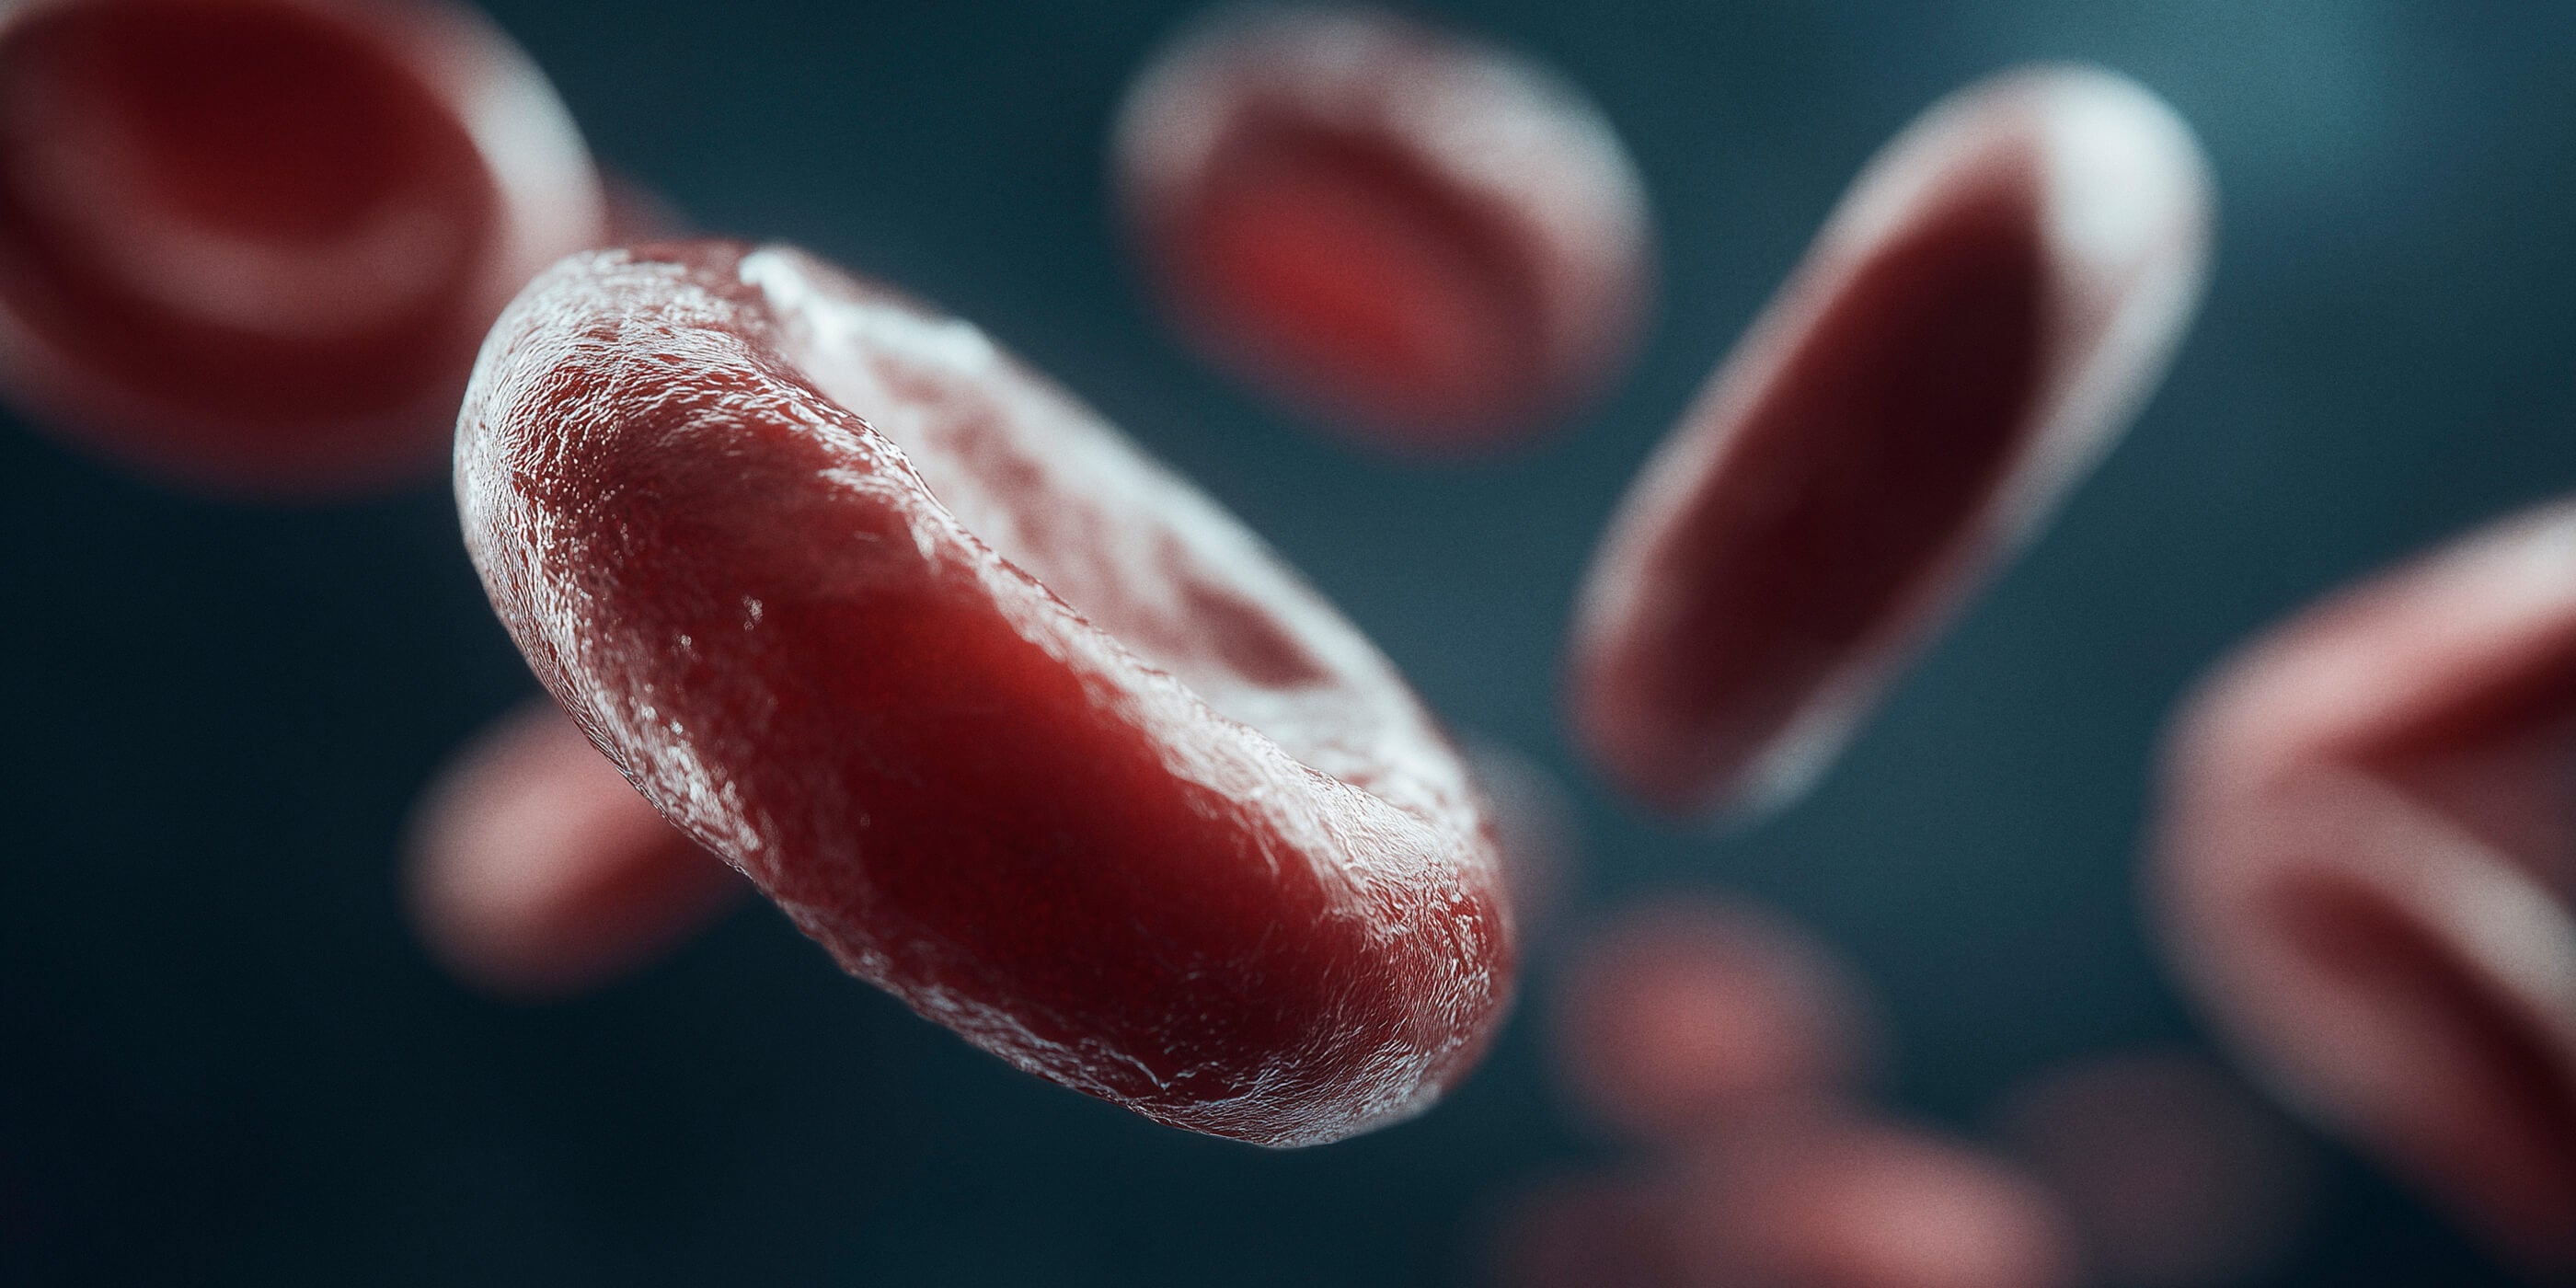

La criopreservación es un servicio que permite guardar y conservar las células madre del cordón umbilical después del parto